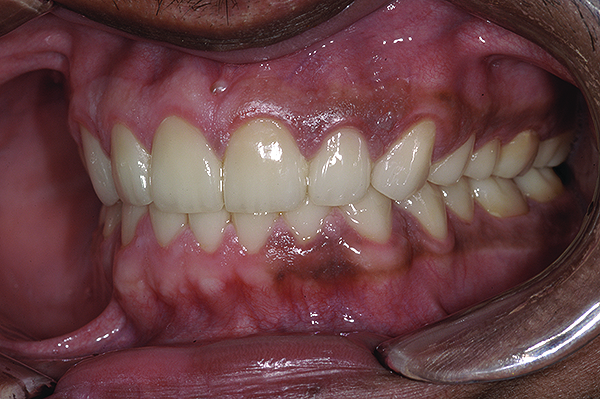

Figure 16. Anterior final restorations bonded.

Figure 16

The anterior restorations were fabricated with low-translucency lithium-disilicate ingots and layered in the incisal half to provide the desired internal characteristics in accordance with the patient’s age. The final anterior restorations were then tried-in and verified for marginal fit, esthetics, and phonetics. After the patient’s approval, they were bonded using dual-cured resin cement (Variolink® II, Ivoclar Vivadent) (Figure 16). Because the enamel in such cases is already compromised, bonding can become clinically unpredictable. A self-etching primer was used on the teeth, followed by a bonding agent (Clearfil™ ST Bond, Kuraray Dental, www.kuraraydental.com) that was light-cured for 20 seconds. The intaglio of the crowns was prepared by etching with 9% buffered hydrofluoric acid for 60 seconds and silanating them to achieve optimum bonds to the resin cement.18

The final restorations depicted restoration of form, function, and beauty, with good harmony of restoration and the periodontium (Figure 19 through Figure 25). MIP was in harmony with CR, and right and left lateral excursion discluded all posteriors with anterior group function. The postoperative orthopantomogram (OPG) (Figure 26) shows the treatment done while maintaining the vitality of anterior teeth.